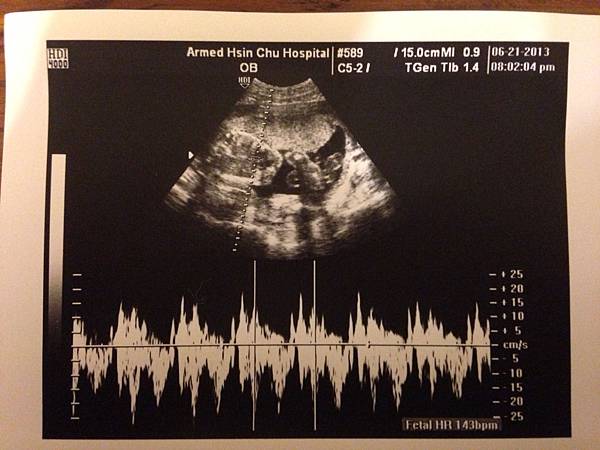

(20130621) 53.8kg "產檢時 54.8kg: 52.4(12w)+0.7(17w)+1.7kg(21w)"

本次開始可以計算頭圍, 肚圍, 跟大腿骨長度來推測重量.

陳小皮頭圍大小約是 22w+... 是說頭真的很大就是了... 而且頭型好好看呦~

心跳 143 下, 體重約 472g. 阿我胖這麼多是胖心酸的嗎@@